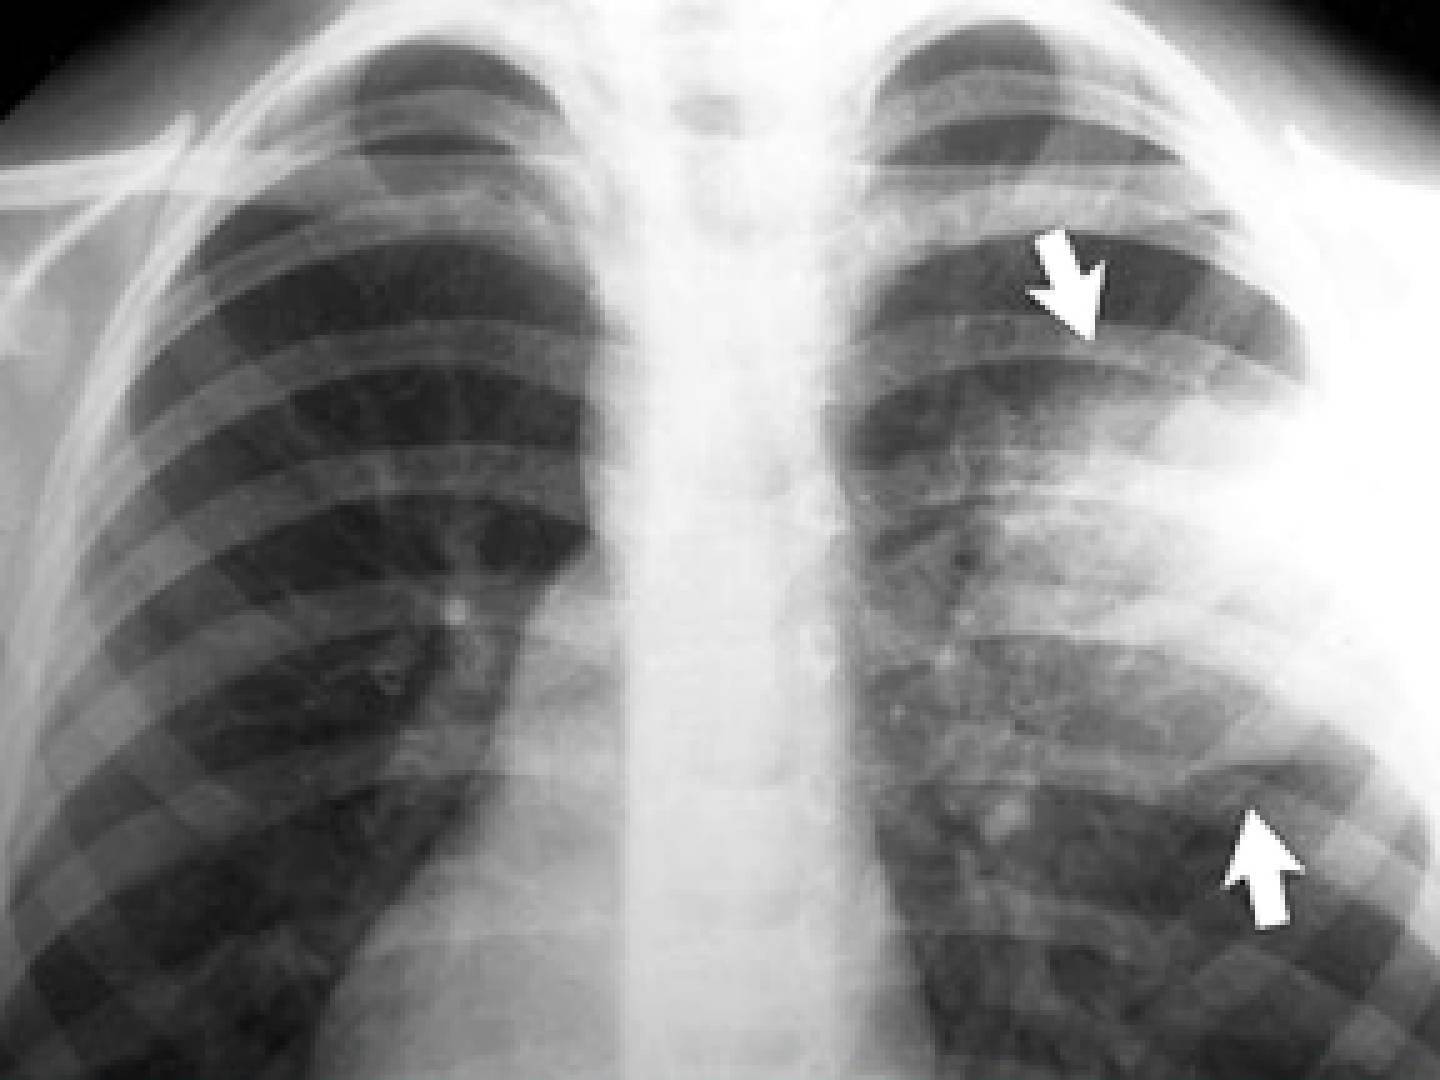

Очаговая

Очаговая (или очагово-сливная) форма пневмонии – очаги инфильтрации имеют диаметр 0,5-1 см и локализуются в одном или нескольких сегментах легкого. Иногда поражения могут располагаться билатерально. Легочная ткань воспаляется катарально, при этом в просвете образуются альвеолы серозного экссудата. Если очаговая форма переходит в очагово-сливную, отдельные участки инфильтрации объединяются в один большой очаг, который нередко может занимать целую долю.

На снимке видны отдельные небольшие очаги поражения (1-1,5 см), расположенные в одном из легких (при билатеральной форме – в обоих). Заметным в данном случае будет расширение корней легких из-за наполнения жидким экссудатом.

Снимок при очаговой пневмонии

На рентген-снимке показана очаговая пневмония.

Очаговая пневмония

Очаговая пневмония встречается чаще всего, она переносится легко, если вовремя начать лечение. Нам часто задают вопрос о том, как выглядит очаговая пневмония на фото, вот её характерные особенности, которые можно увидеть на снимках:

- появление теней и значительное нарушение прозрачности на некоторых ограниченных участках;

- значительно увеличенный в размерах корень легкого, но только на той стороне, где наблюдается поражение;

- сильная деформация и усиление легочного и бронхиального сосудистого рисунка.